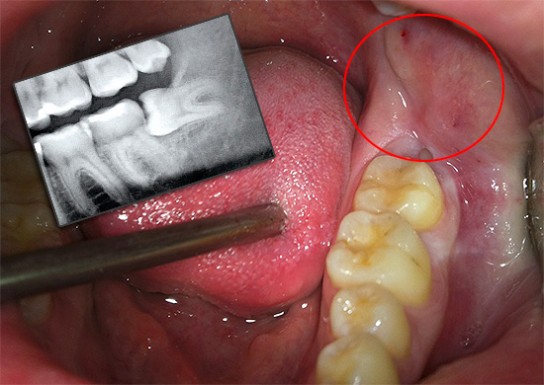

Признаки появления новых коренных зубов обычно включают в себя ноющую боль и отек десен, особенно в задней части ротовой полости. Когда зубы мудрости прорезываются правильно и для них достаточно места, эти симптомы, как правило, быстро проходят.

Однако у многих людей не хватает пространства в деснах для новых коренных зубов. Иногда зубы мудрости могут расти неправильно – наклоняясь в сторону щеки или располагаясь горизонтально.

В некоторых случаях, если третьи моляры растут неправильно или наносят значительный ущерб деснам, могут развиваться инфекции на деснах или в области челюстной кости, что требует немедленного обращения к врачу.

Также стоит обратить внимание на ситуации, когда новый зуб травмирует щеку, так как это может привести к воспалению или заражению.

Если вы испытываете сильную боль и дискомфорт в месте прорезывания, рекомендуется обратиться к стоматологу. Специалист проведет осмотр десен и, возможно, направит на рентген, чтобы оценить рост зуба и наличие пространства для него.

Если места недостаточно, зуб растет неправильно или есть инфекция, его удаление может быть необходимым, чтобы предотвратить смещение других зубов, что может негативно сказаться на прикусе и вызвать серьезные стоматологические проблемы.